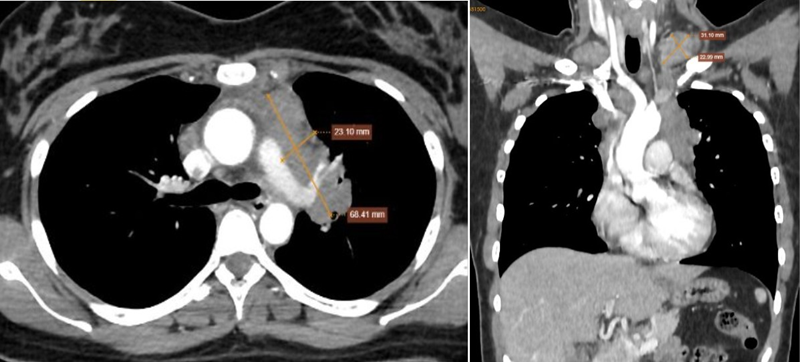

CT ghi nhận vùng nền cổ, thượng đòn hai bên có nhiều khối hạch bất thường, bờ đa cung, ngấm thuốc không đồng nhất sau tiêm, hạch lớn kích thước khoảng 32x45mm

Chụp CT toàn thân có tiêm cản quang phát hiện nhiều hạch bất thường vùng nền cổ, hố thượng đòn hai bên và trung thất, các hạch tạo thành đám ôm quanh các mạch máu trong trung thất và ôm quanh phế quản gốc hai bên.